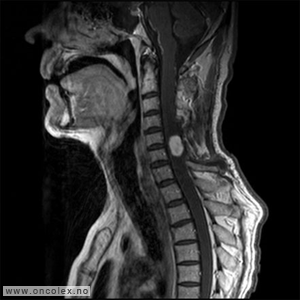

MR er det viktigste diagnostiske hjelpemiddel for å påvise svulst i ryggmargen, ryggmargsnervene og ryggmargshinnene. CT kan også brukes, men har klare begrensninger når det gjelder fremstilling av svulstene. Blant annet kan svulster som ikke tar opp kontrast bli oversett. CT og skjelettrøntgen kan imidlertid være nyttig for å kartlegge grad av skjelettødeleggelse og eventuell instabilitet i ryggsøylen.

Bildeeksempler